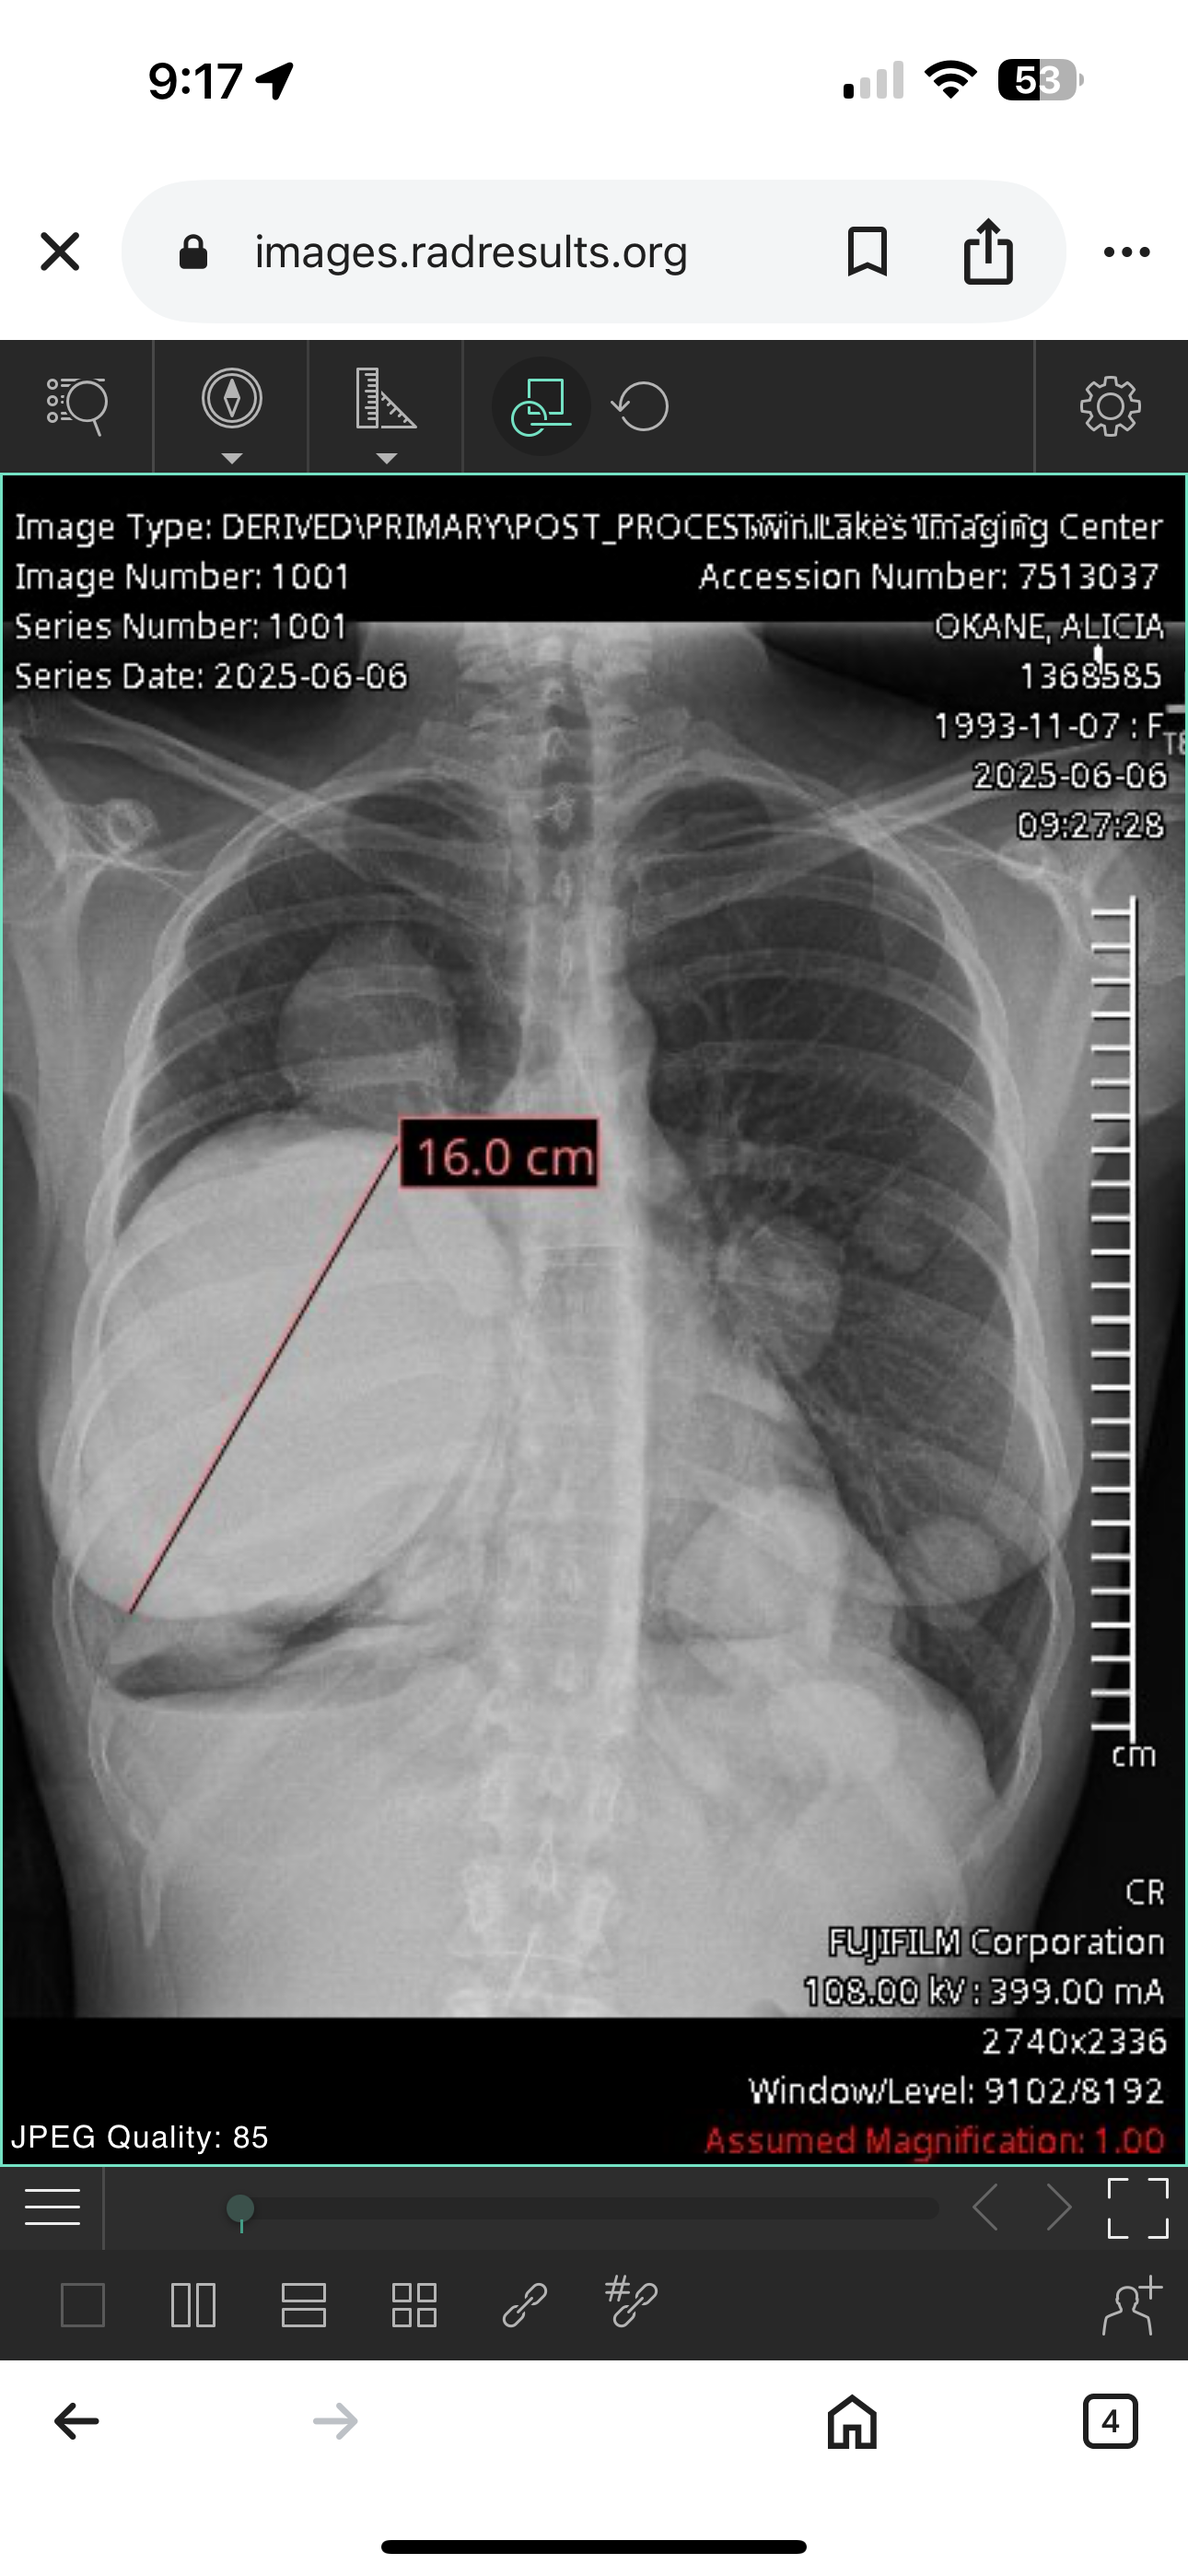

Our beautiful friend Alicia O’Kane is fighting for her life after being diagnosed with metastatic high-grade leiomyosarcoma of the lungs, a rare and very aggressive cancer.

However, the cancer came back — this time in her lungs. Since then, Alicia has gone through six grueling rounds of treatment, with three more still to go, hoping to shrink the tumor and buy more time. Even with all of that, her doctors fear she may only have 1–2 years left, despite these incredibly tough and risky treatments.

One of her treatments had to be stopped because it started causing excruciatingly painful symptoms and could lead to heart failure. But stopping it means the tumor could keep growing and spreading. It’s an impossible situation that no one should ever have to face.